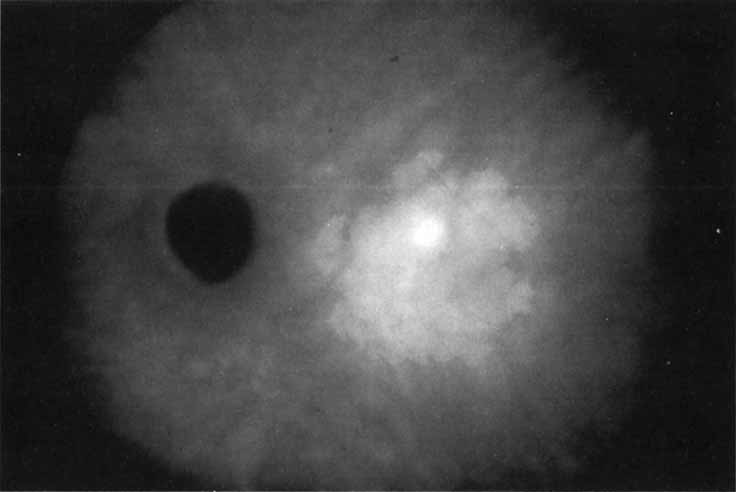

Unlike fluorescein angiography, however, ICG angiographic studies have pointed out that certain principles of laser photocoagulation treatment may not hold with this new imaging capability. This is particularly true with the concept that all areas of CNV need to be obliterated to achieve a successful anatomic result. A careful evaluation of ICG angiograms in some patients with occult CNV has revealed that two forms of neovascular lesions may exist: (1) localized, intensely hyperfluorescent leaking areas of “active” CNV; and (2) more subtle and larger areas of hyperfluorescence with minimal leakage, representing “quiescent” portions of the neovascular complex (Fig. 8). A pilot study by Guyer and colleagues22 demonstrated that localized photocoagulation treatment applied to the active area of CNV alone might result in successful and long-term anatomic stabilization and improvement in the visual acuity in some patients (Fig. 9). A subsequent review of these lesions has demonstrated that they may represent a subpopulation of occult CNV known as polypoidal choroidal neovascularization, described later.